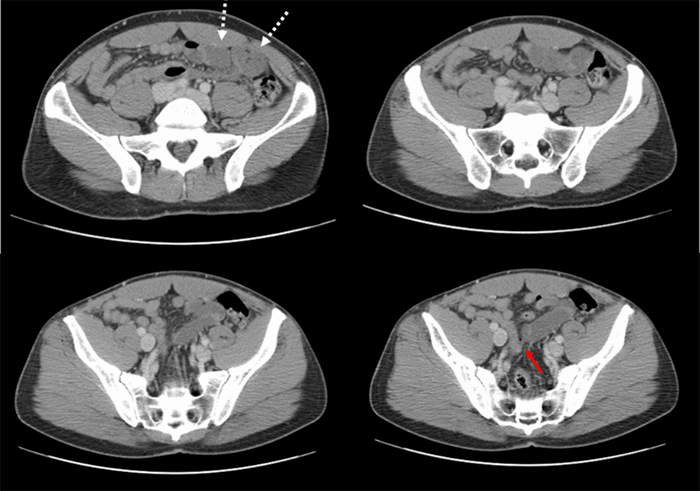

The patient is a 37-year-old male with no significant past medical history and no past surgical history who presented to the emergency department with a one-day history of severe, sharp, cramping epigastric pain with associated nausea and emesis. The patient did note similar episodes of abdominal pain one month prior that resolved spontaneously; he did not seek medical attention at that time. At presentation, he was afebrile and hemodynamically stable. Laboratory evaluations were unremarkable, including a normal white blood cell count without eosinophilia. A CT scan of the abdomen and pelvis was obtained with IV contrast, showing dilated loops of small bowel with suggestive transition point in the mid-small bowel. The radiologist also noted possible partial midgut malrotation and several prominent central mesenteric lymph nodes (Figure 1 and Figure 2). The patient was resuscitated with intravenous fluids, electrolyte repletion, and nasogastric decompression with plans for operation intervention. He improved clinically over the first night of hospitalization.

Figure 1. Axial images from computed tomography scan of the abdomen and pelvis with IV contrast showing dilated loops of small bowel (dashed white arrows) and suspected transition point (solid red arrow).